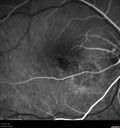

29 year old female reports that the right eye became blurry with a "funny feeling" about a weeks ago which has progressed to central grey spot. History of PCOS, Endometriosis, possibly Fibromyalgia. 1 healthy 2 year with unremarkable pregnancy. No pain OD except on the first day the patient noticed decreased. Patient had flu-like symptoms after Thanksgiving 2017 and went to Urgent Care in AZ after she became worse. Has taken amoxicillin antibiotic since Urgent Care visit 11/30/17. Patient had rashes on hands and feet as well as chest. Felt she had "little cuts" on hands and feet. VA 20/200 OD, 20/32 OS. Vision in the right eye improved to near normal within 1 months and elevated titers of Coxsackie B3 and B4 titers.

uaim-2_weekslater.png

Unilteral Acute Idiopathic Maculopathy - 2 weeks following other images454 views00000